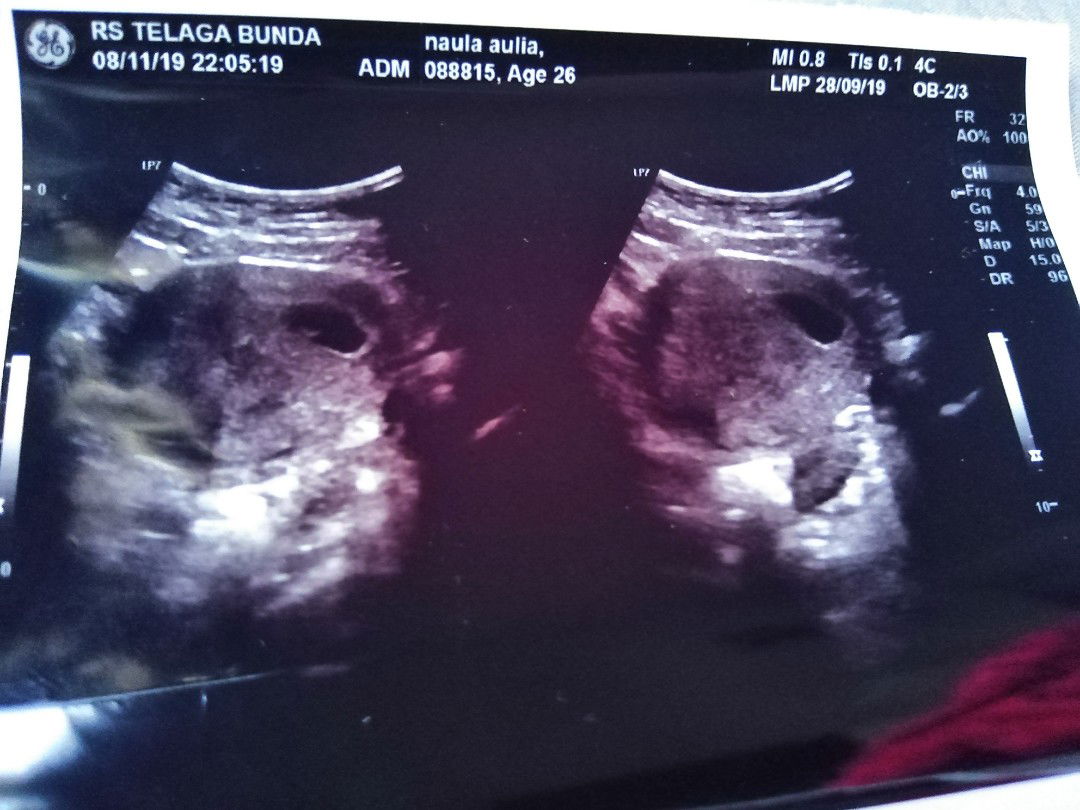

MasyaAllah hari ini rasa sakitnya luar biasa.. Divonis BO hari kamis. Dan dikasih obat untuk peluruhan alami. Sy ga minum, Tetep sy pertahankan. Tapi kemarin sy merasakan sakit pinggang yg luar biasa disertai kram perut. Sy siang ke bidan dan disarankan usg ktna katanya gejala keguguran. Sorenya saya usg dan dinyatakan tetap BO dan bahkan kantung semakin menciut dan bentuk tidak beraturan. Akhirnya hari ini hari pertama saya konsumsi obat.. MasyaAllah rasanya.. ? Semoga sy kuat tanpa suami disamping yg bekerja diluar kota.. ?